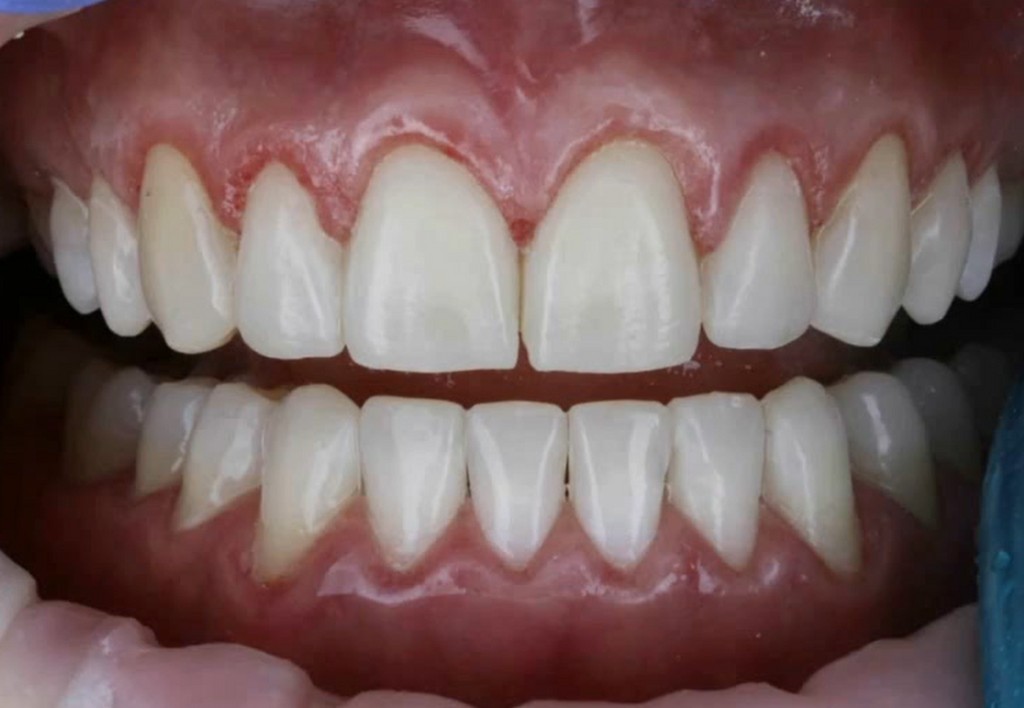

Galleria fotografica

Il Dott. David Geštakovski si laurea in Odontoiatria presso la School of Dental medicine di Zagabria e si occupa di estetica dentale. È specializzato in faccette in composito e utilizza la Injectable Technique, è docente e relatore internazionale in diversi workshop e webinar.